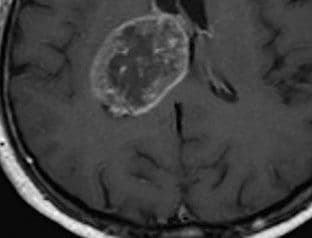

Zasad samo pet odsto pacijenata sa GBM uspijeva da preživi duže od pet godina, a prosječno očekivano vrijeme preživljavanja je 15 mjeseci. Čak i uz primjenu agresivnih terapija, ovaj vid raka je praktično neizlječiv, te stoga otkrivanje slabosti njegovih ćelija predstavlja suštinski važan korak u razvoju nove i efikasne terapije ljekovima.

Komponenta koja je privukla pažnju naučnika nazvana je “Vakinol-1” i svakako ubija ćelije raka, i to na način kakav dosad nije zabilježen. Ovi molekuli, naime, isključuju sposobnost ćelije da kontroliše šta ulazi i izlazi kroz njene ćelijske zidove, tako da se ovakve ćelije na kraju bukvalno raspadaju-rasprkavaju, a ono što je značajno jeste da okolno, zdravo tkivo pritom ostaje potpuno neoštećeno. (Blic)